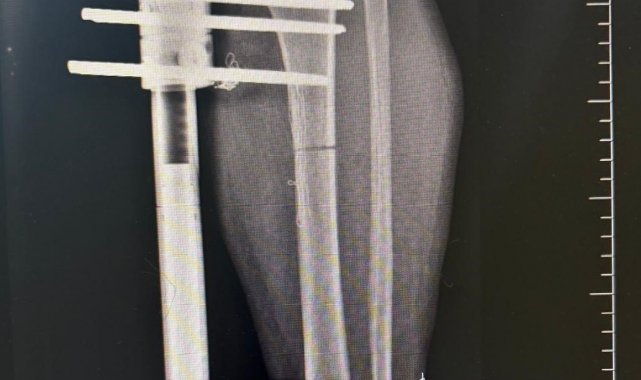

Ameliyat aşamasının ardından gerçekleşen süreci tek tek dile getiren Ortopedi ve Travmatoloji Uzmanı Prof. Dr. Mahmut Argün, "Hastamız 1.58 boyunda olması nedeniyle sürekli boyunun kısalığından dolayı hem fiziksel hem de bedensel rahatsızlıkların olduğunu dile getirdi. Israrla boyunun uzatılmasını bizden talep eden hasta 2 aşamalı olunması gereken muayeneyi 1 aşamalı olmasını istedi. Sol tarafından başlayarak hem femur hem de tibia 5 ila 6 santimetre arasında uzatmayı planladık. Hastamızı ameliyata alıp bu işlemleri gerçekleştirdik. Hasta şuanda uzatma işlemlerinin yapılabilmesi için malzeme yerleştirme aşamasını gerçekleştirdik. Ameliyattan 10 gün sonra uzatma işlemlerini başlayacağız. Uzatma işlemleri yaklaşık 60 gün sürecek. Uzatma işlem süreci geçtikten sonra işlemi durdurup kaynaması için 2-3 ay bekleyeceğiz. Ardından ise hastanın üzerinden malzemeleri yaklaşık 150-200 gün arasında çıkaracağız. Bu tarz işlemler meşakkatli ve özen isteyen ameliyatlar" diye konuştu.

Uzama sürecinde her gün 1 milimetre olmak üzere kurulan mekanizmanın başladığını dile getiren Ortopedi ve Travmatoloji Uzmanı Op. Dr. Necip Özateş, "Her gün 1 milimetre olmak üzere, üzerindeki mekanizma üzerinden hem uyruk kemiği hem kaval kemiği uzatılmaya başlıyor. Hem bu şekilde kemik uzaması hem de bu esnada kemik kaynaması aynı anda olduğu için daha kontrollü bir işlem oluyor. Hedef uzunluğa ulaştığımızda uzatma işlemini sonlandırıyoruz. Sonrasında da kemiğin kaynaması sürecine geçiyoruz" dedi.

İlk 4 hafta üzerine bastırmadıklarını ardından ise kontrollü bir şekilde sürecin ilerlediğini belirten Op. Dr. Necip Özateş, "İlk etapta ameliyatın erken dönemlerinde ilk 4 haftaya kadar üzerine bastırmıyoruz. Ondan sonraki günlerde yavaş yavaş hasta koltuk değnekleri yardımı ile destek alarak üzerine basmaya ve günlük yaşantısına daha rahat devam etmeye başlıyor. Yapılan ameliyat bir vatandaşın günlük hayatına etkileyen bir şey değil. Bu süreç hastanın da bilgisi dahilinde özen ve biraz daha sabır gerektiren bir süreç. Bu konuda hastayla fikirde varıldığı zaman gayet iyi sonuçlar elde ediyoruz" ifadelerini kullandı.